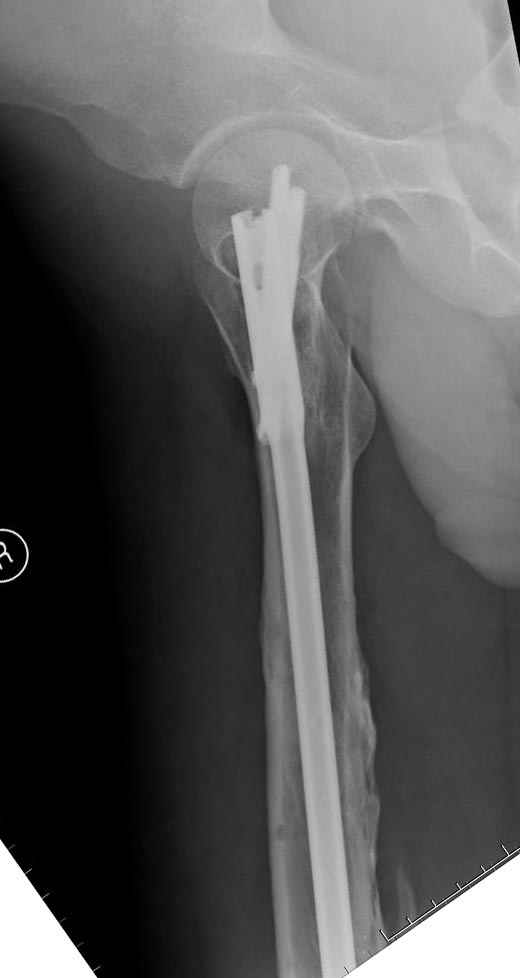

На следующий день произвели интрамедуллярный остеосинтез: этапы во время операции (рис №8, №9)

и последующих снимках (рис №10, 11, 12, 13) перелом сростается и передвигается с полной нагрузкой.

При обзоре причин перелома, на снимке №2 обнаружили, что один из стержней аппарата наружной фиксации проходил только через передний кортекальный слой, что создало стрессовую зону на бедре и в результате перелом из-за незначительной травмы.